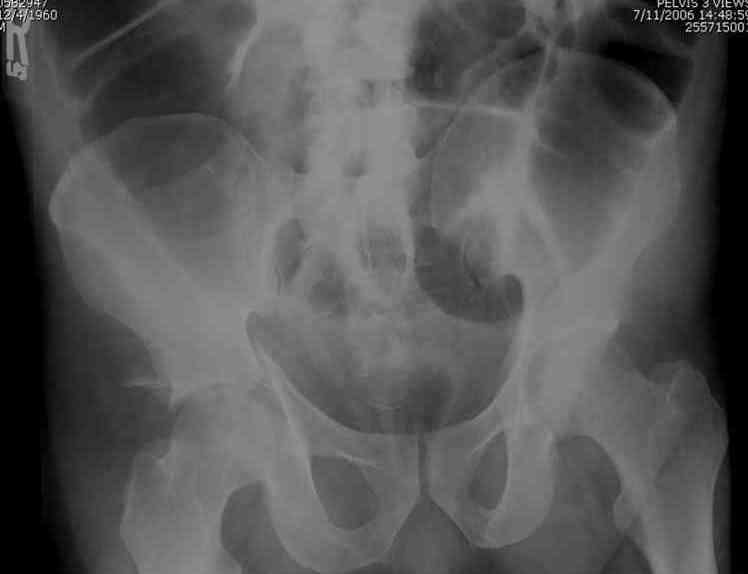

The 2nd example is of a motorcyclist with a transverse fracture-dislocation...he had a closed attempted reduction and placed in traction but the manipulative reduction was not concentric (not unusual for this injury pattern)...so the traction was adjusted to be just enough to disengage the head from the fracture (12#) until he could be cleared for surgery one day after injury...he was treated "urgently" then with a prone KL, clean the fracture, reduce and clamp it, screw it, support with a balanced plate, close, and enjoy...2-3hours, 400cc EBL, blah, blah, blah..